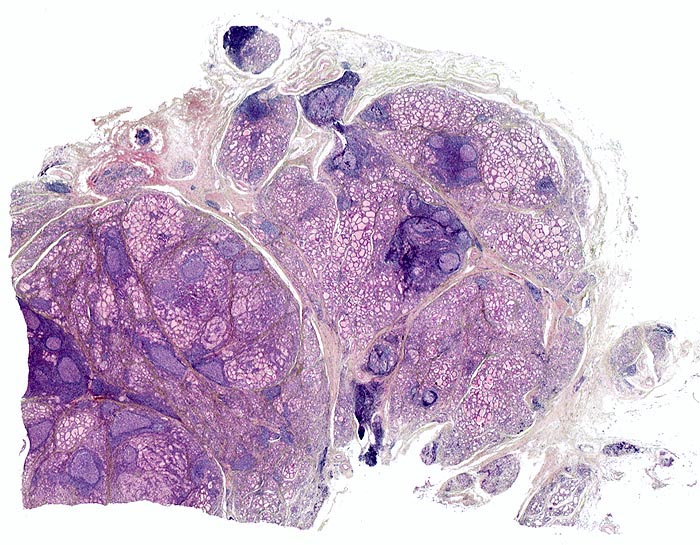

Bei kleiner Vergrösserung fällt eine angedeutet knotige Struktur des Gewebes auf. In diese knotige Grundstruktur eingebettet sind immer wieder dichte Infiltrate von Lymphozyten und Plasmazellen («blaue Herde») und eindeutige Lymphfollikel mit Keimzentren. Es besteht eine geringe Parenchymfibrose.